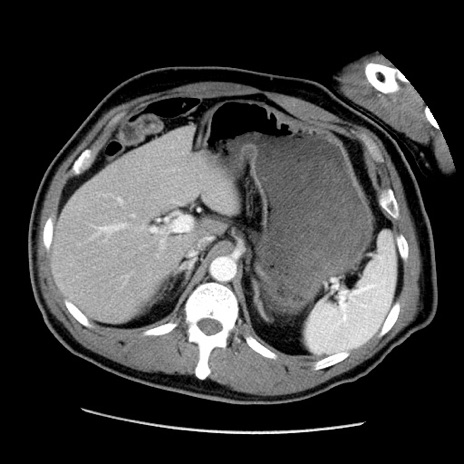

症例22(横断像)

【症例】50歳代男性

【主訴】腹痛

【現病歴】AVMからの被殻出血のため回復期リハ病棟入院中。 本日午後3時頃急に下腹部痛が出現した。

【既往歴】AVM、被殻出血、虫垂炎、高血圧

【身体所見】意識晴明、左半身不全麻痺、会話の理解は良好、36.5°C、腹部:膨隆、全体に板状硬、下腹部正中に圧痛点あり、反跳痛-、筋性防御不明、右下腹部にope scar

【データ】WBC 9400、CRP 0.06